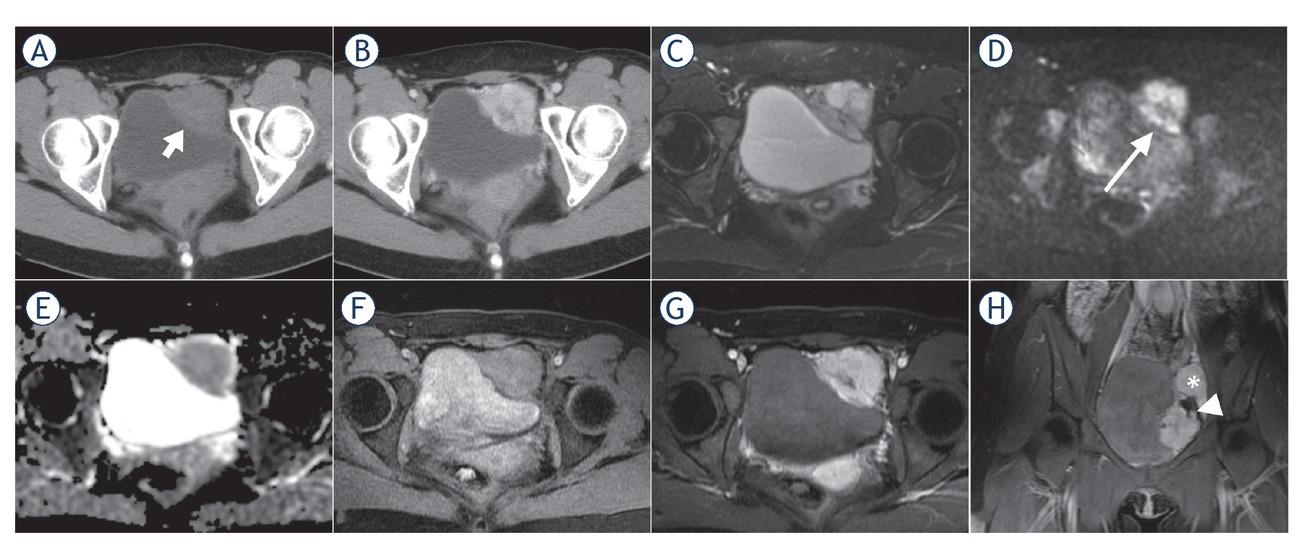

CT and MR image characteristics*

| Computerized tomography (n = 13) | |

|---|---|

| Density | Moderate or slightly lower density |

| Enhancement characteristics | Moderate to marked enhancement |

| Calcification | None |

| Cystic degeneration or necrosis | Rare (n = 2) |

| Haemorrhage | None |

| Magnetic resonance imaging (n = 8) | |

| T2-weighted imaging | Slight hyperintensity |

| Diffusion-weighted imaging | Hyperintensity |

| Apparent diffusion coefficient (ADC) map | Hypointensity (ADC value, 0.883±0.126×10-3 mm2/s)** |

| T1-weighted imaging | Slight hyperintensity |

| Enhancement characteristics | “Fast in and slow out” pattern |